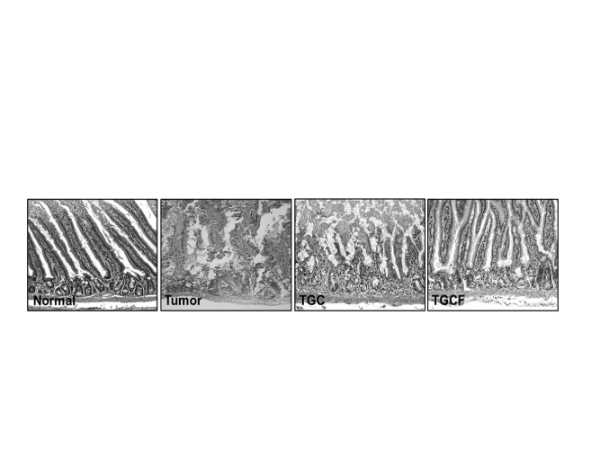

Nomal: 正常腸絨毛結構

Tumor: 罹癌之腸絨毛結構

TGC: 罹癌後合併兩種化療藥物治療之腸絨毛結構

TGCF:罹癌後合併兩種化療藥物,並投予小分子褐藻醣膠之腸絨毛結構